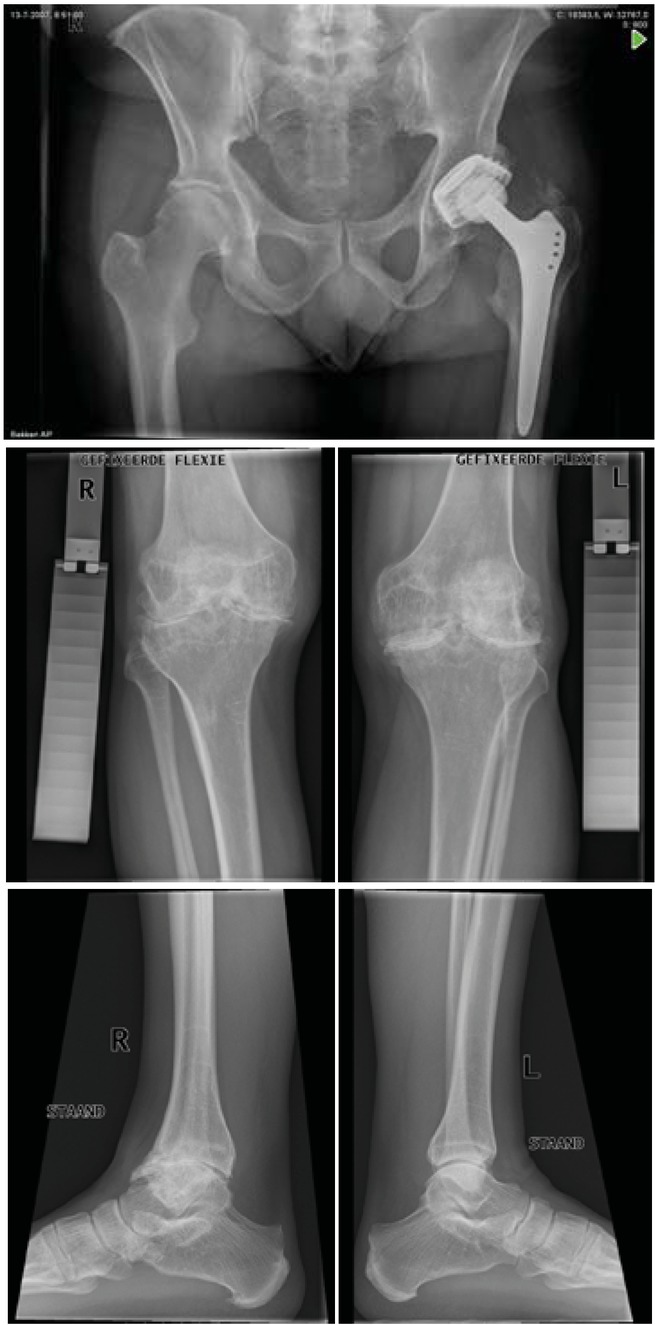

Figure 5

Case 2 X-rays before (2009) and after (2010) bilateral total knee arthroplasty (type Genesis II (centered) with patella button)

Case 2 – Bilateral TKA

This case is that of a single, unemployed man aged 60 years at time of MJP. He underwent rehabilitation in hospital: physiotherapy focused on AROM for two weeks, standing, transfers and walking (walking aid) until discharge. He was admitted to a rehabilitation centre three weeks post-surgery, where he received daily physiotherapy and hydrotherapy sessions combined in weekly programmes. At home he then received regular sessions with a local physiotherapist as well as hydrotherapy at UMCU. He returned to regular group hydrotherapy sessions after 6 months.

The patient is now very positive and says: -‘’A miracle happened to me’.’ He goes out more frequently and recently played percussion in a standing position for 3 hours. He was riding an adapted bike, with the saddle positioned rearward, as getting on proved easier, but was able to ride a regular bike when his adapted bike was stolen. He has adaptations to his orthopaedic shoes and his ankle pain is slowly progressive.

Post-operative pain assessment scores on the VAS (0–10) was on average 0.3 (range 0–1), indicating minimal pain in all cases. Retrospectively pain improved of all the joints operated on: Case 1: LK 3 and 1 (△= 2) and RK 3 and 1 (△= 3); Case 2: LA 2 and 0 (△=2) RA 2 and 0 (△=2); Case 3: LK 3 and 0 (△=3) and RK 3 and 0 (△=3). The active range of motion of four knees (cases 2 and 3) increased between 5 and 10 degrees, and extension 0 till 20 degrees. As a result of the fixation of the tibiotalar joint, active range of motion decreased in case 1; plantar flexion average 15˚ (range 10– 20˚) and dorsiflexion average 7.5˚ (range 5–10˚).